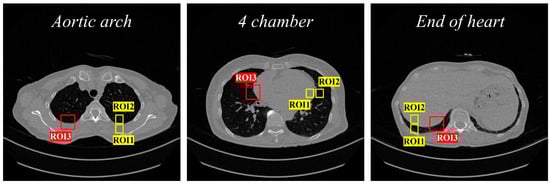

where S A and σ A represent the average and standard deviation of the signal strength in the target area, respectively; S B and σ B represent the average and standard deviation of the signal strength in the background area, respectively. In addition, the ERD is a representative factor that can evaluate the degree to which the boundary part of the image is preserved; it can be defined as the distance between the points representing 10% and 90% of the CT number. The region of interest (ROI) for measuring the CNR and ERD is shown in the CT sample image in Figure 2.

Figure 2. ROI area set in each CT sample image (CNR evaluation: ROI1 and ROI2, and ERD evaluation: ROI3).